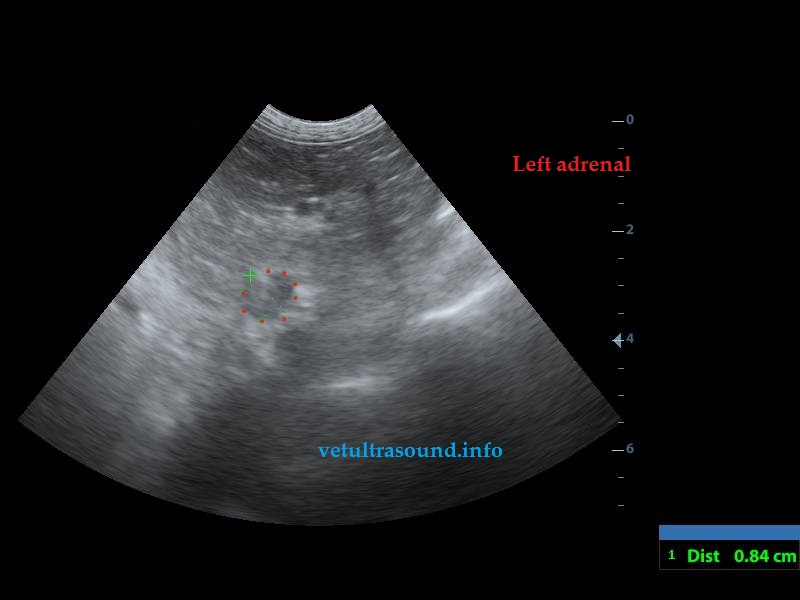

There was a mild Increase in the diameter of the caudal pole of both adrenal glands.(pic2-3)

Αύξηση των ορίων της εγκάρσιας διαμέτρου του οπίσθιου πόλου των επινεφριδίων.(pic2-3)